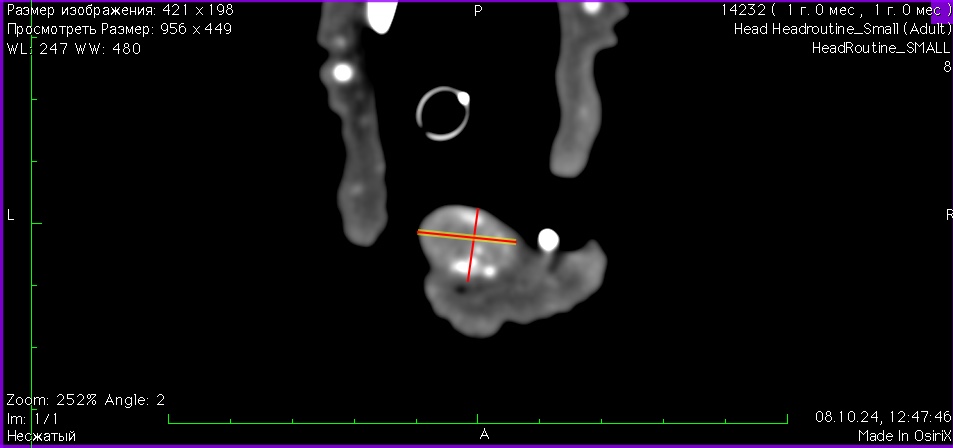

- 08.10.2024 обращение с жалобой на растущее новообразование на нижней челюсти. Осмотр выявил признаки новообразования размером 16 x 12 мм на ростральной части нижней челюсти справа, поражая клык и область резцов. (изб. 8). Проведена частичная ростральная мандибулэктомия. Морфологический диагноз – амелобластома, границы резекции содержат опухолевый рост.

Изображение 8. Резцы нижней челюсти 301, 302, 303 и 401 отсутствуют. Между резцом 402 и клыком 304 наблюдается лизис и периостальная реакция нижней челюсти. На этом уровне также выявляется мягкотканевое образование размером 16 x 12 мм с умеренным кровотоком и множественными кальцификатами.